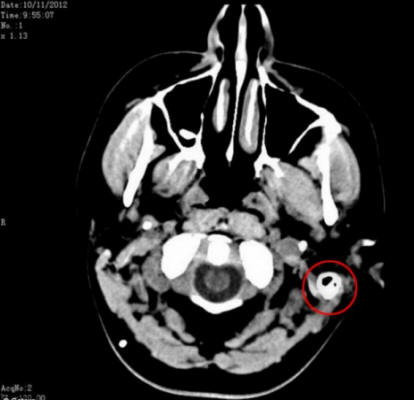

Sama so napotili k številnim strokovnjakom, ki so sumili so, da ima morda možganski tumor. Na srečo po z izvedbo vrste testov je bil možganski tumor izključen iz seznam možnih vzrokov bolezni. Vendar zdravniki tega niso mogli določi, kaj se ji je zgodilo. Strokovnjaki so ugotovili resnico vzrok njenih zdravstvenih težav šele po ledvenem delu punkcija.

Človeški možgani so obkroženi s tekočino, ki ščiti možgane da bi udaril v steno lobanje, vendar se je izkazalo, da je Samino telo to tekočino proizvede trikratno normo. Tudi po diagnosticiranje in jemanje 17 različnih zdravil na dan, Sam še naprej trpel grozne glavobole.